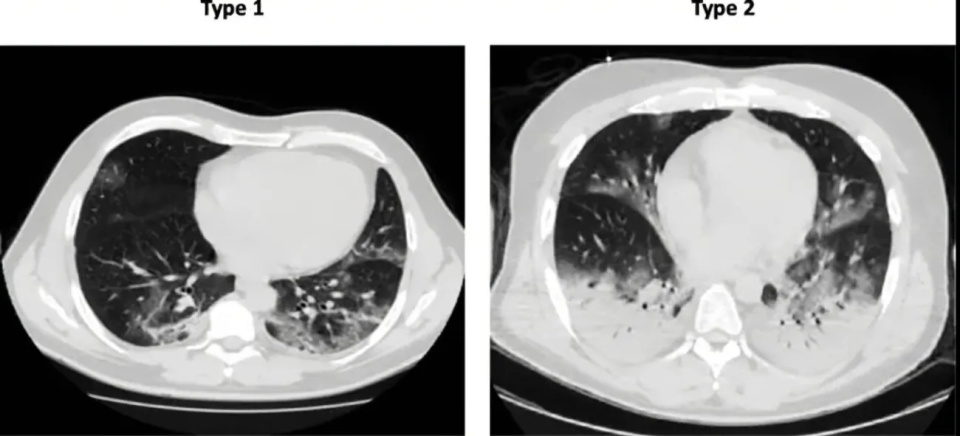

这里张医生提到的肺炎指的是一种由病毒、细菌、真菌等病原体所导致的感染性肺实质炎症,在影像学上往往表现为新近出现的、肺部浸润影。在临床治疗中,需要与放射性肺损伤,药物性肺损伤,免疫性肺损伤等非感染性炎症相鉴别,一旦发生误诊,后果其实同样是不堪设想的。